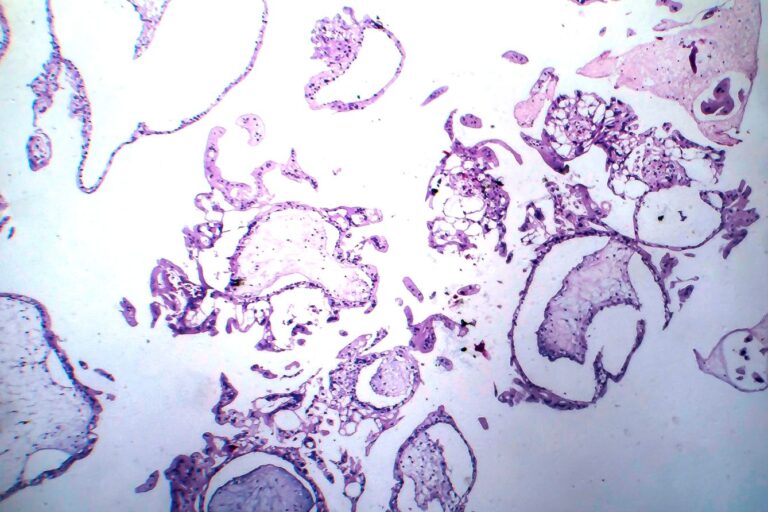

W efekcie galaktoza i jej toksyczne metabolity odkładają się w tkankach, prowadząc do uszkodzeń wątroby, nerek, ośrodkowego układu nerwowego i soczewki oka.

- powiększenie wątroby,

Jeśli choroba nie zostanie wykryta i leczona, może prowadzić do ciężkich powikłań, takich jak sepsa czy niewydolność wątroby. Dlatego tak ważne są badania przesiewowe w pierwszych dobach życia.